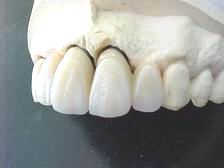

Munhões personalizados

Prótese metalocerâmica personalizada